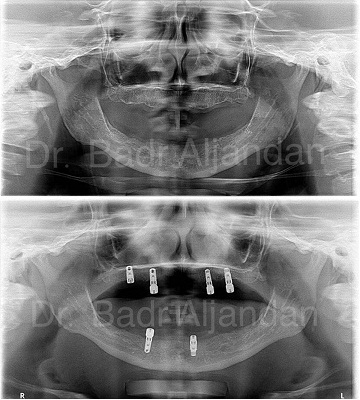

غرسات الأسنان مصنوعة من مادة التيتانيوم. توضع داخل عظام الفك في نفس مكان الأسنان المفقودة. الجزء المعدني الموجود داخل عظام الفك يعمل كوتد بديلا لجذر الأسنان. يتم تركيب الجزء المعدني بواسطة عملية جراحية داخل الفك. وبعد فترة يتم ترابط عظام الفك مع الجزء التيتانيوم مسببا تثبيت قوي للجزء الصناعي داخل الفك. الجزء الأوسط يثبت وتد قوي للأسنان الصناعية.

مراحل تركيب الغرسات (الزرعات) من الأوتاد إلى الأسنان الصناعية